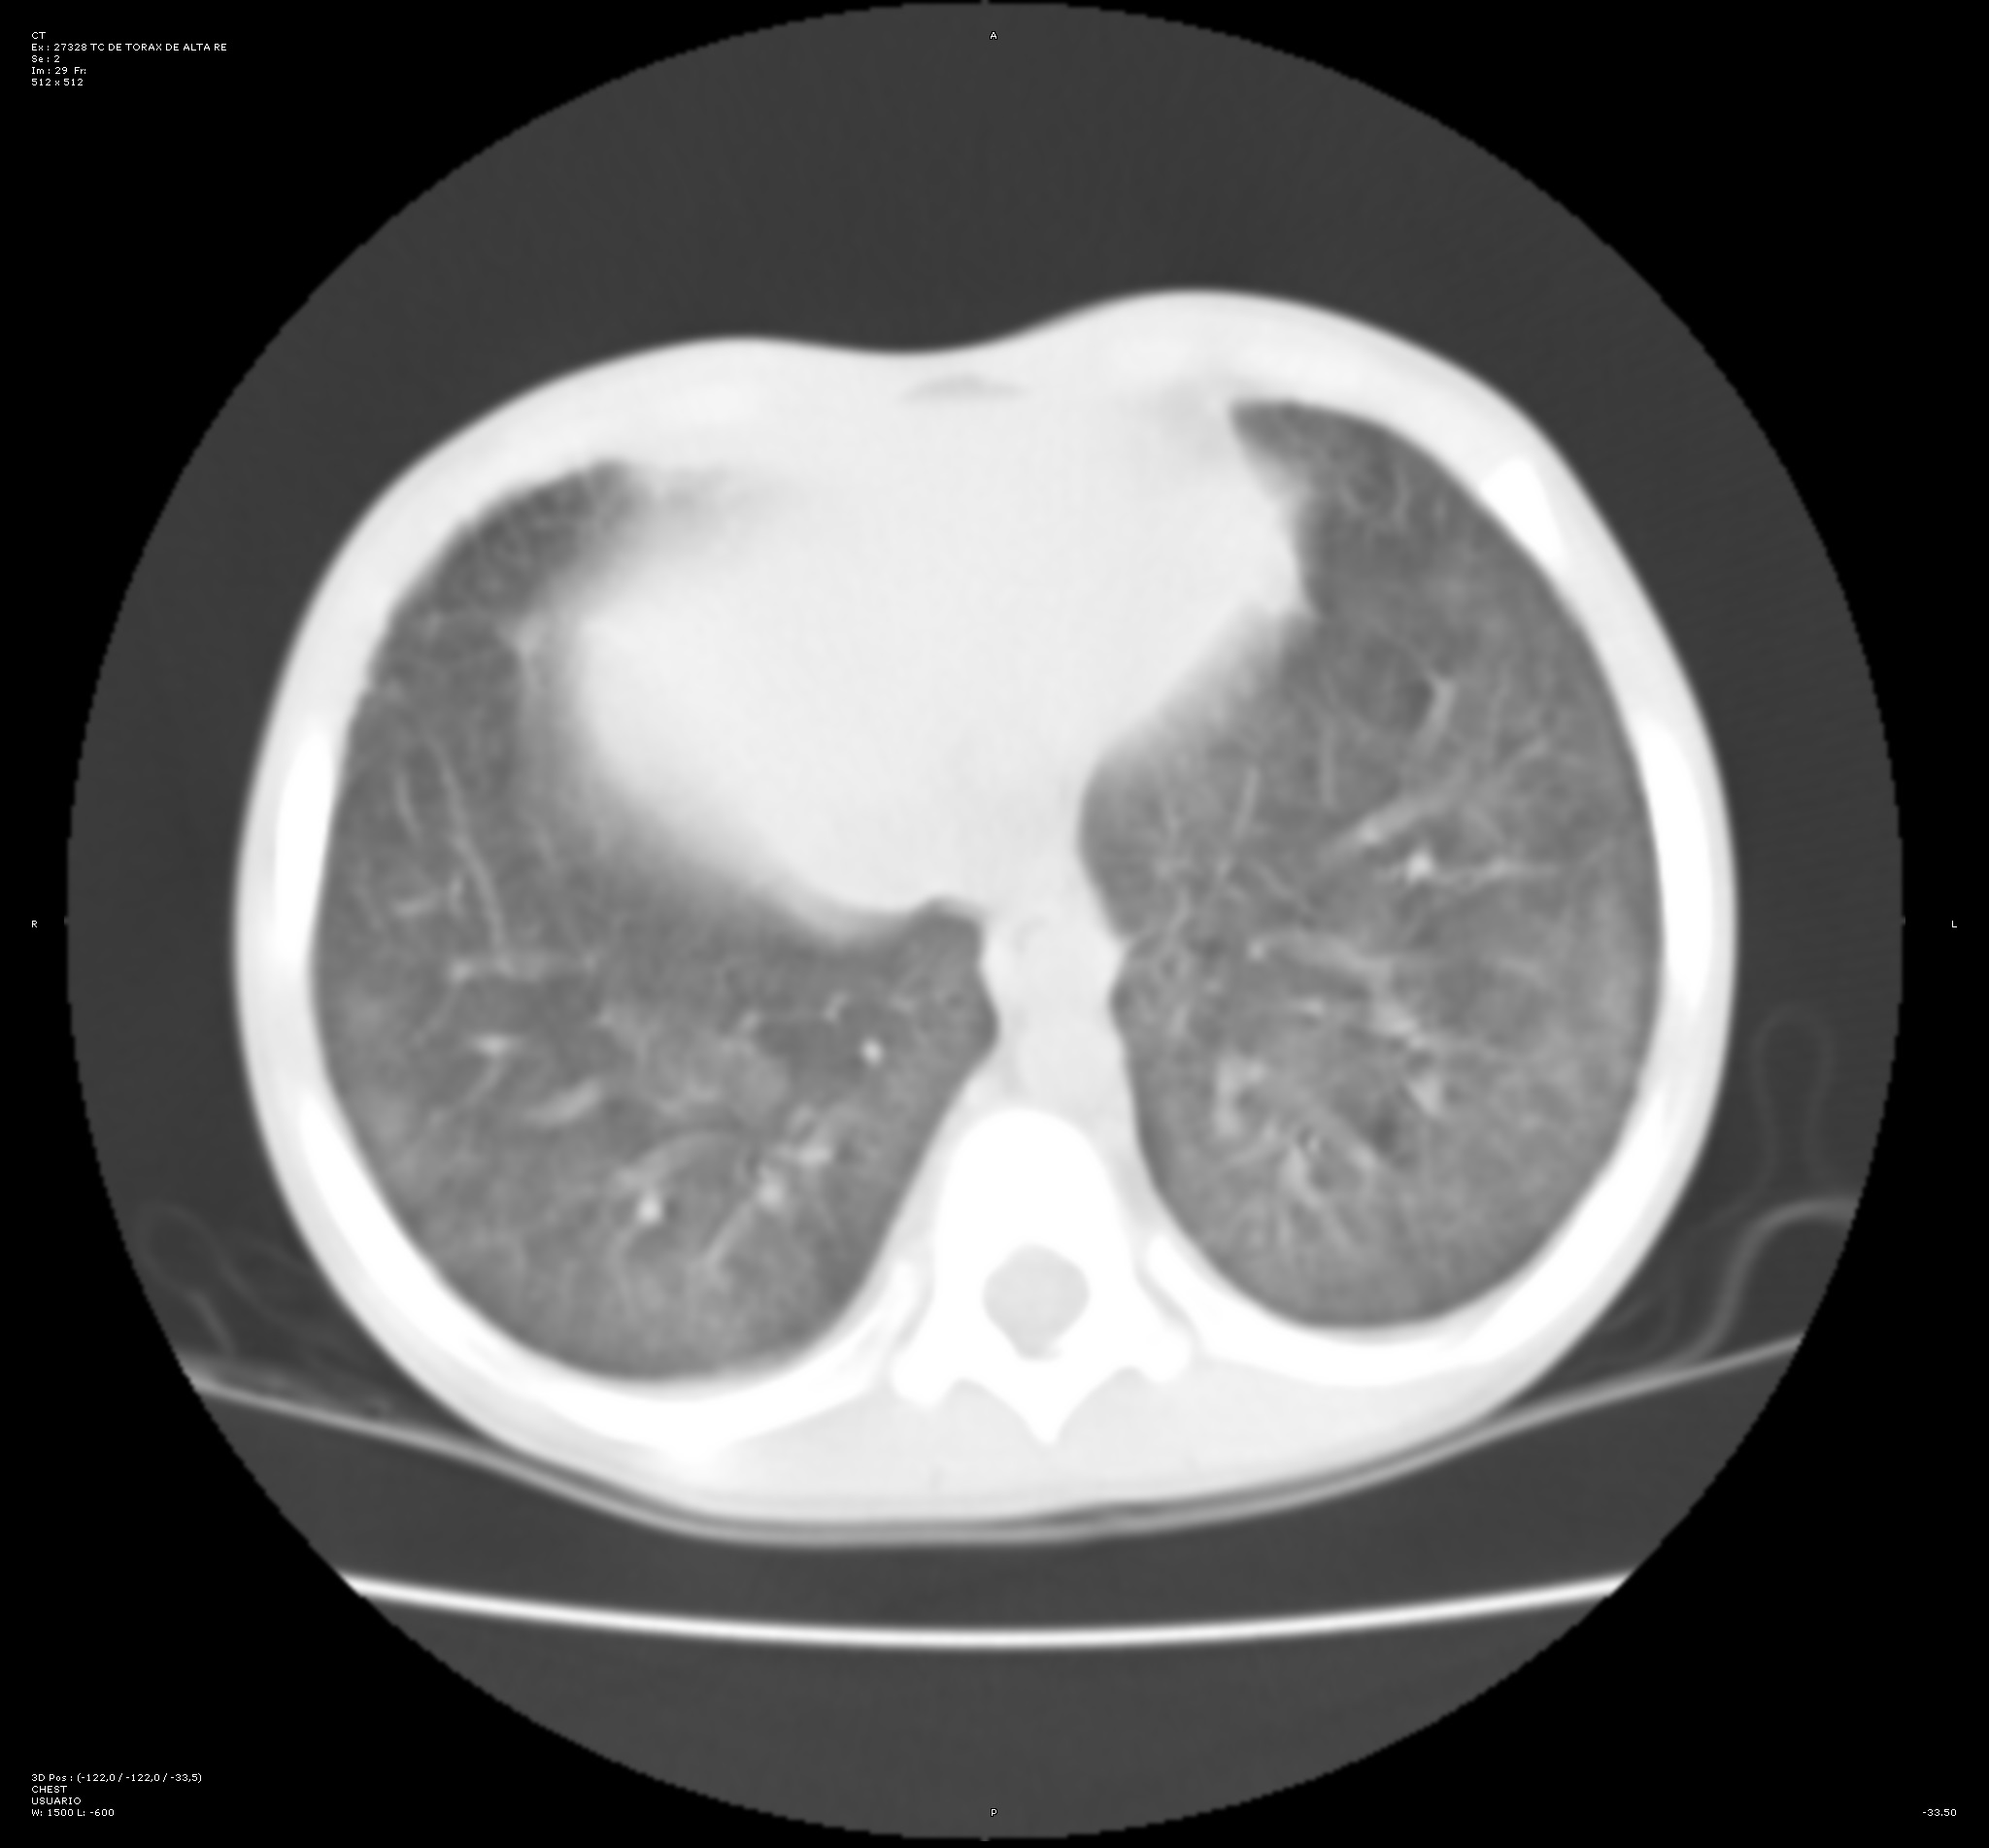

Con intención de no realizar en primer lugar una prueba invasiva que pudiera inestabilizar al paciente, se decide llevar a cabo una tomografía computarizada (TC) de tórax. En esta prueba se visualizan opacidades bilaterales parcheadas y simétricas en vidrio deslustrado de predominio en campos posteriores y basales. Este hallazgo incrementa la sospecha de hemorragia alveolar difusa.